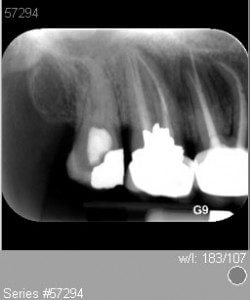

end-case-7-a